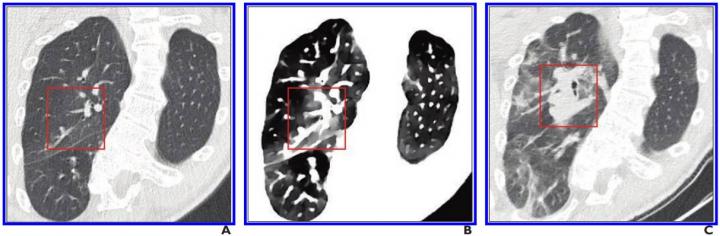

image: A, Initial conventional axial CT image shows no noticeable lung damage (within red box) in right upper lobe. B, Electron density spectral CT image obtained at same time as image in A shows lesions (within red box) in right upper lobe. C, Follow-up conventional axial chest CT image obtained 5 days after images in A and B confirm presence of lesions (within red box) in right upper lobe.

In all four patients, their pulmonary lesions (45 ground-glass opacities, overall) were more conspicuous on electron density images than on initial conventional CT images and were clearly confirmed on follow-up conventional CT images. Moreover, lesion extent, assessed via semiquantitative reporting scale denoting surface area involvement for each lobe, was easier to ascertain on electron density images. With Daoud and colleagues' results indicating electron density imaging improves early assessment of the extent of ground-glass opacities that could be missed by conventional CT, electron density showed the most promising results by enhancing the contrast of ground-glass opacities compared with the normal lung.